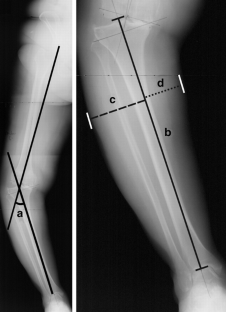

Anteroposterior radiographs that included the whole tibia were taken before and after 75 total knee arthroplasties in 48 patients. The same tibial extra-medullary alignment guide system was used in every knee. The average tibial component alignment was 0.4 (SD 2.5, range −4.9 to 6.4) degrees of valgus post-operatively. 59 tibial components (78.7%) had a tibial cut within 3 degrees from being perpendicular to the mechanical axis, ten were too valgus (13.3%) and six were too varus (8%). The chance of the tibial components becoming too varus was higher if there was lateral tibial bowing, compared with no tibial bowing (p = 0.048). A smaller lateral width of the leg increased the chance of the tibial components becoming too valgus (p = 0.047).

Fig. 2